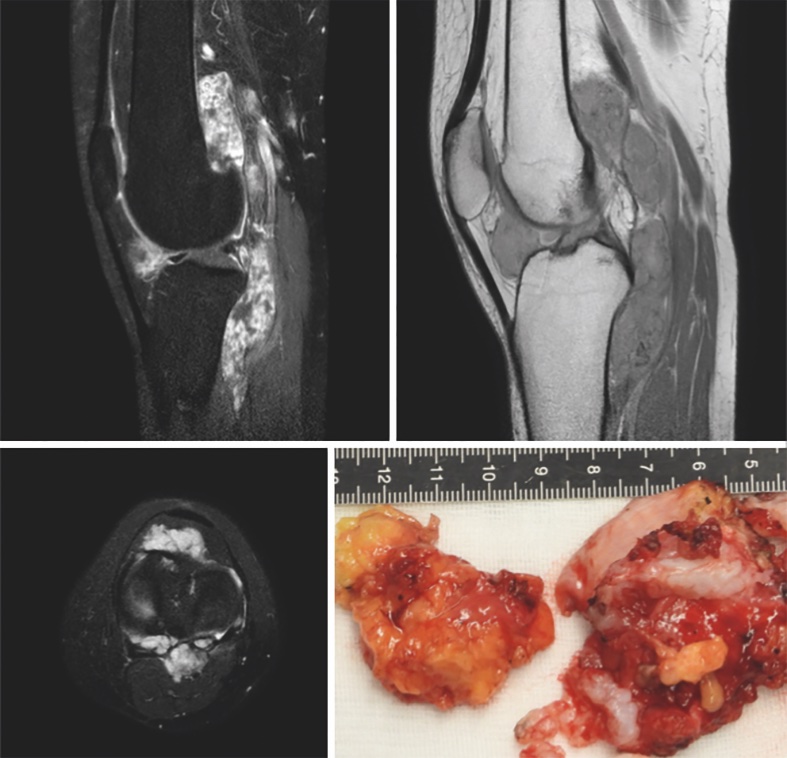

È un tumore benigno composto da cellule mononucleari simil-sinoviali che interessa solitamente articolazioni le guaine dei tendini e le borse mucose. È la terza lesione in termini di frequenza tra quelle benigne dei tessuti molli. Dal punto di vista epidemiologico non dimostra predilezione per il sesso, colpisce solitamente giovani adulti tra 20 e 40 anni di età ma può essere diagnosticata anche in età più avanzata. La terminologia moderna, ovvero il nome di tumore a cellule giganti delle guaine tendinee si riferisce ad una lesione in passato nota come sinovite villonodulare pigmentosa; la nuova terminologia è stata evidenziata nel Blue Book (Soft Tissue and Bone Tumors) della WHO Classification of Tumors già da alcuni anni3,4. Questa malattia preferenzialmente si localizza nell’articolazione dell’anca e del ginocchio e nelle parti molli delle mani o dei piedi, pur potendo interessare anche altre sedi. La sede di gran lunga più frequente è il ginocchio dove caratteristicamente le masse nodulari o i piccoli noduli di TGCT si localizzano sia anteriormente al ginocchio nel recesso sovra-quadricipitale, posteriormente alla rotula e intorno al corpo di Hoffa sia posteriormente al ginocchio dove tendono a localizzarsi in profondità nelle adiacenze del legamento crociato posteriore. Il quadro clinico tipico nel ginocchio è una sensazione di impaccio, talora dolorosa e/o associata ad un deficit di flessione o di estensione (Fig. 2).

Il riscontro di masse sia anteriormente sia posteriormente nell’articolazione del ginocchio è pressoché patognomonico per la diagnosi di TGCT, laddove invece il riscontro di un nodulo o di più noduli solo anteriori o posteriori pone in modo stringente il problema della diagnosi differenziale con un Sarcoma Sinoviale. Questa patologia è particolarmente frequente fino al 70% dei casi in sede intra-articolare e le articolazioni più frequentemente interessate sono il ginocchio e l’anca, più raramente la tibiotarsica4. Anche il sarcoma sinoviale può crescere lentamente e simulare il comportamento biologico e il pattern di crescita di una lesione benigna.

La diagnosi differenziale si pone anche nei confronti di altre forme di sinoviti aspecifiche e/o proliferative. Tra queste ultime la condromatosi sinoviale si caratterizza e differenzia per la presenza di aree di calcificazioni evidenziate all’imaging (in particolare TC e RMN e talora Rx) dovute alla natura cartilaginea del tessuto. L’agobiopsia dirime la diagnosi differenziale in modo definitivo8-11.